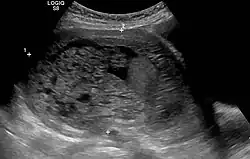

Blasenmole im Ultraschall

Die Diagnose wird über erhöhte Werte für das humane Choriongonadotropin (β-hCG) sowie über die Darstellung der verdickten Plazenta in Ultraschalluntersuchungen gestellt.